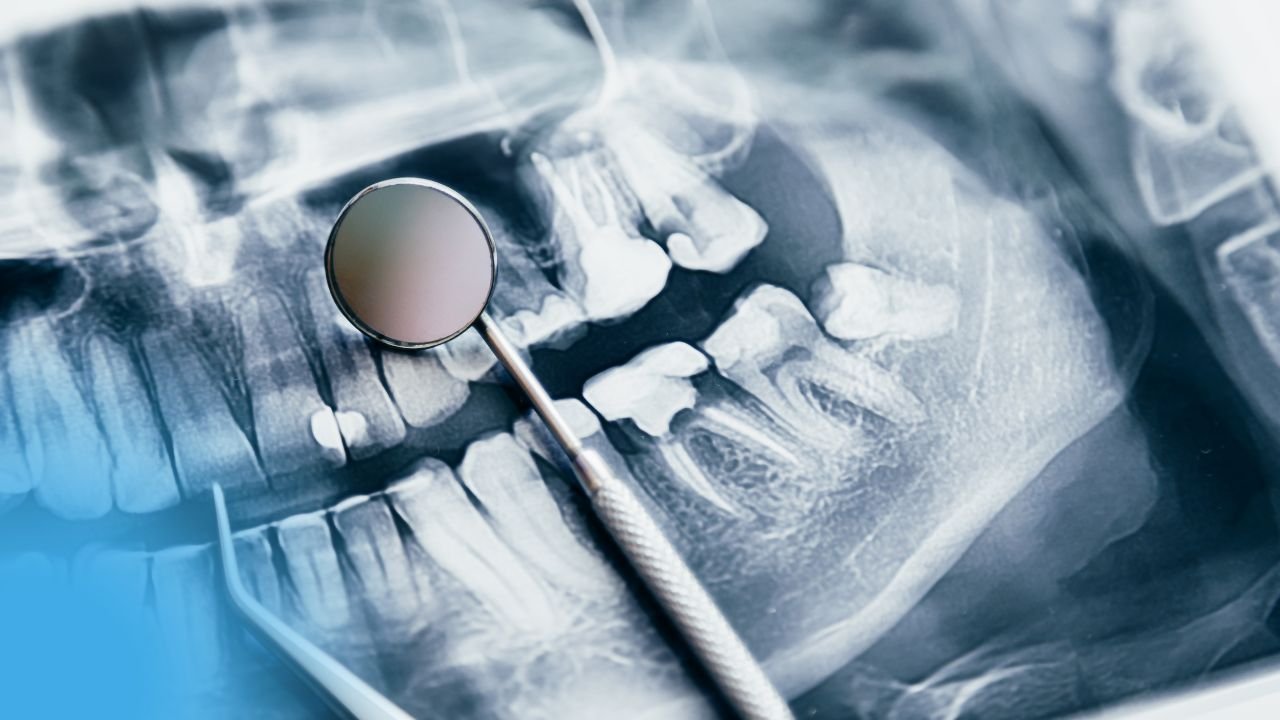

Examen visuel approfondi : Il cherchera des fissures, des espaces entre l’obturation et la dent, des signes d’usure ou de corrosion sur vos plombages gris.

Radiographies si nécessaire : Elles révèlent ce qui est invisible à l’œil nu, comme les caries sous les obturations ou autour des racines.